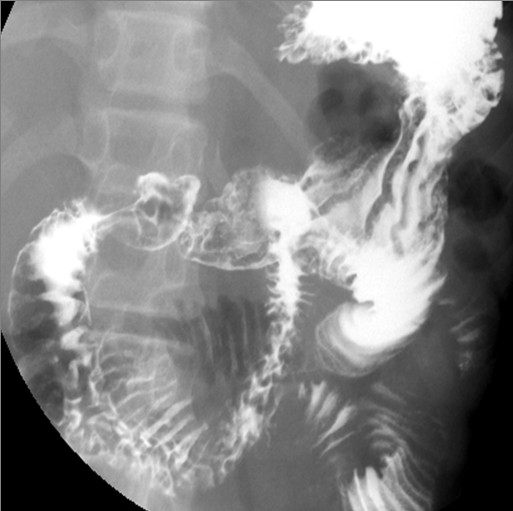

十一天开始不间断呕吐,腹胀,基本不能自主排便,这是做的钡剂检查结果